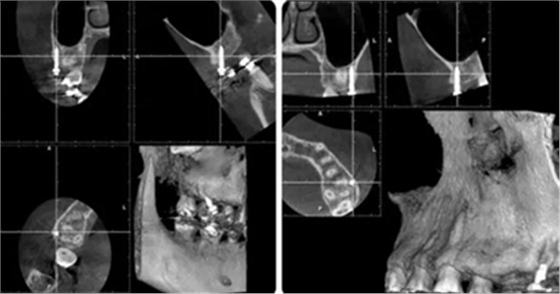

治療8個(gè)月,換0.018*0.025"CuNiTi弓絲,植入支抗釘,植入位點(diǎn)為上頜第一磨牙根上方顴牙槽嵴處,使其與牙根平行。同時(shí)嘗試性牽引遠(yuǎn)移上牙列。

(3)全牙列遠(yuǎn)移種植釘植入位點(diǎn)為上頜第一磨牙根上方顴牙槽嵴處,使其與牙根平行,在術(shù)前需CBCT確認(rèn)骨量,否則有脫落或無法植入的可能。